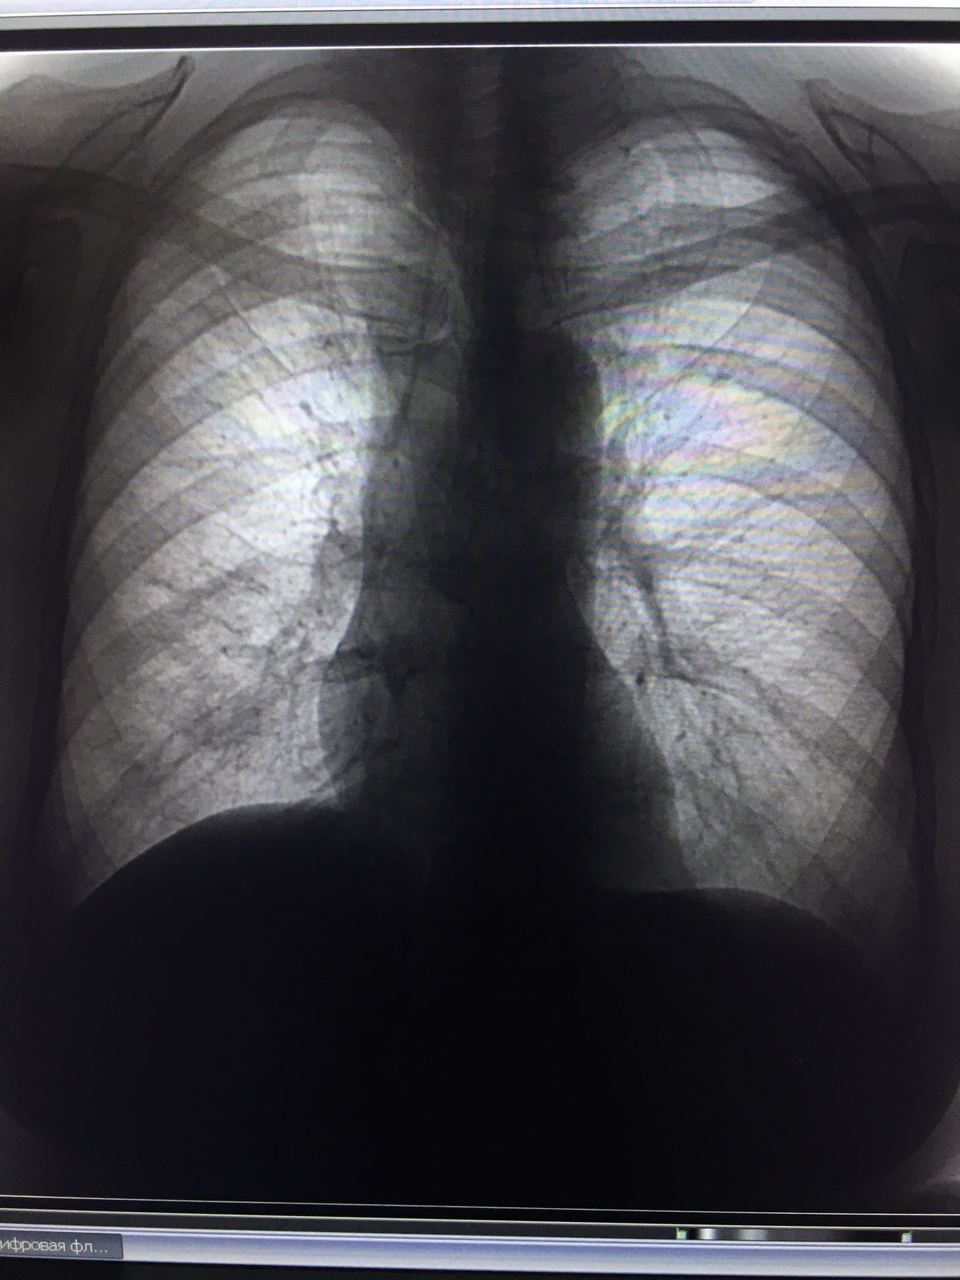

Добрый день, подскажите пожалуйста, есть ли инфильтрация? Или такой рисунок? Женщина, 1957 гр, жалобы на одышку в течение месяца, кашля и температуры нет

само по себе эта локализация (нижние отделы слева) самая коварная, поэтому надо по мягче с вердиктом

Смущает такая асимметрия и достаточно выраженное как будто снижение пневматизации

согласен, скиалогически весьма очевидно, но хорошо бы боковым подтвердить